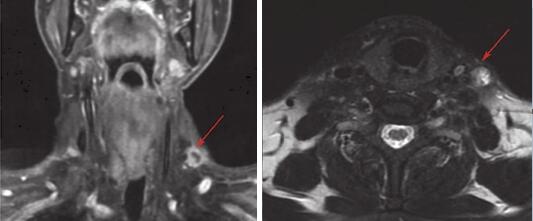

入院后完善基线检查,2015-11-04完善颈部增强CT及MRI检查:下咽部治疗后改变,双侧颈部、左锁骨上淋巴结肿大(图2)。胸腹盆增强CT示双肺多发小结节(图3)。

图2 颈部增强MRI(基线)

注:提示左锁骨上、颈部多发淋巴结(箭头指示为靶病灶)。